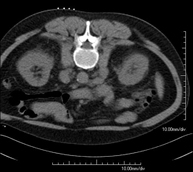

- Abdomen y pelvis- TC Abdomen Prueba diagnóstica que consiste en obtener imágenes del abdomen de alta definición anatómica (hígado, vesícula biliar, vía biliar, páncreas, bazo, estómago, intestinos, riñones, estructuras vasculares, vejiga, útero y ovarios, etc.) mediante el empleo de un equipo de TC (Tomografía Computarizada). Dichas imágenes se estudian posteriormente en una estación de trabajo que permite reconstrucciones bidimensionales en diferentes planos del espacio, y también reconstrucciones 3D (volumétricas). La mayoría de estudios requieren el empleo de contraste yodado para mejorar la definición de las imágenes. Prueba diagnóstica que consiste en obtener imágenes del abdomen de alta definición anatómica (hígado, vesícula biliar, vía biliar, páncreas, bazo, estómago, intestinos, riñones, estructuras vasculares, vejiga, útero y ovarios, etc.) mediante el empleo de un equipo de TC (Tomografía Computarizada). Dichas imágenes se estudian posteriormente en una estación de trabajo que permite reconstrucciones bidimensionales en diferentes planos del espacio, y también reconstrucciones 3D (volumétricas). La mayoría de estudios requieren el empleo de contraste yodado para mejorar la definición de las imágenes.